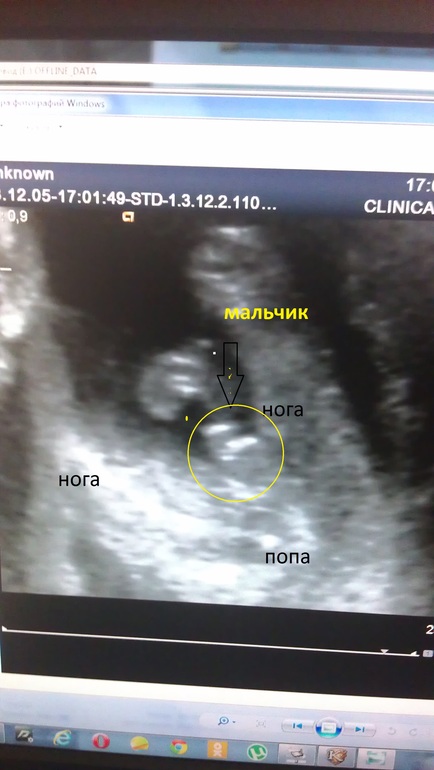

Насчет пола получилось смешно. Как она только не приближала чтоб посмотреть)) картинка крупная цветная. Разворачивает значит мне картинку и спрашивает: "Что видите?". А я вижу отчетливо два больших яичка))) говорю "Мальчик???". Врач говорит: "Да, думаю что 90% мальчик..." потом начинает вертеть картинку с разных ракурсов и говорить: "А вот так - прям девочка, точно прям как девочка... у них ведь еще нет прям явного "хозяйства", только бугорки, и то почти одинаковые))" В общем оставила нас в неведении еще на полтора месяца)))

а вот так понятней?